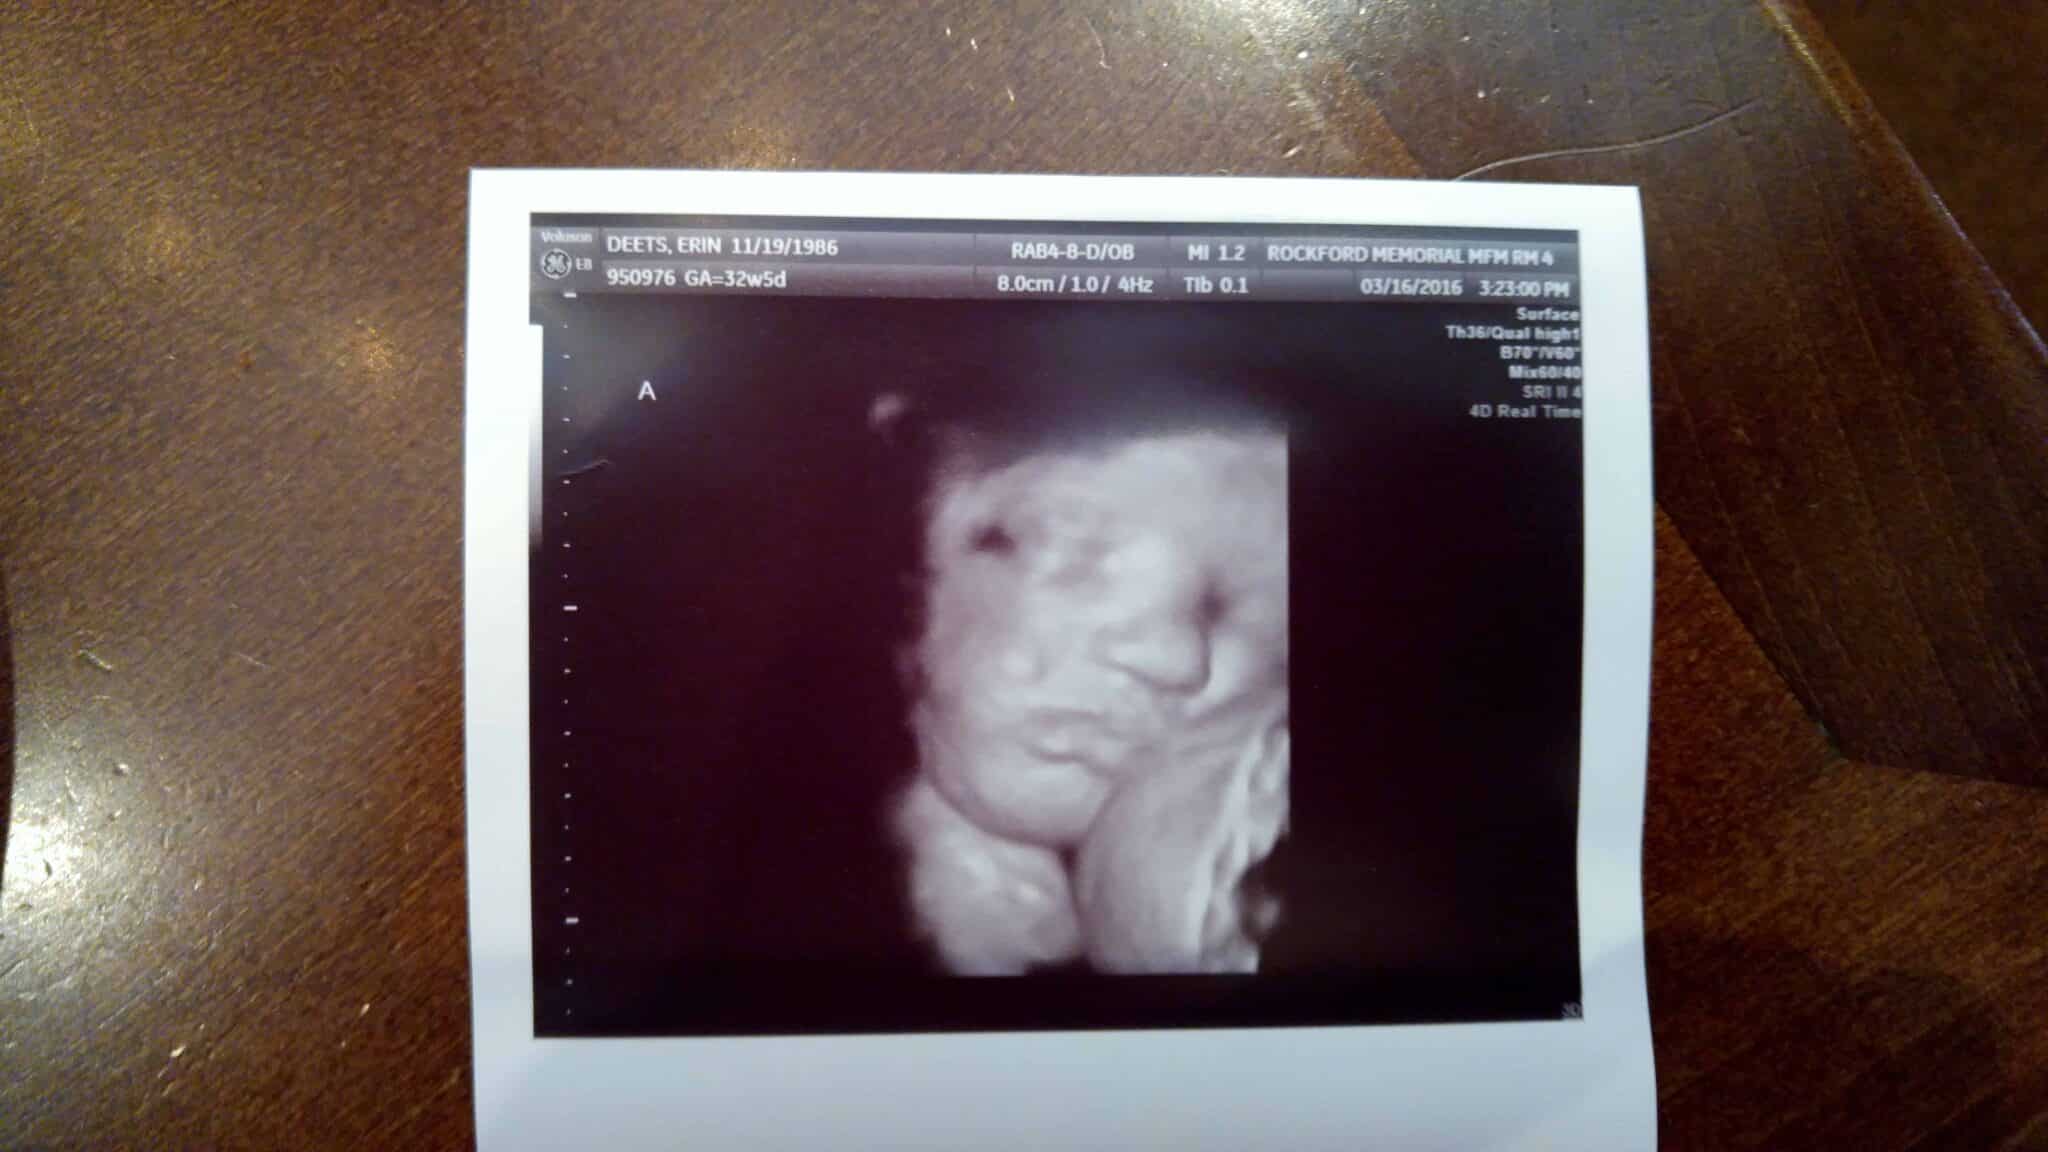

- Ultrasound Photos at 32 Weeks Pregnant With Twins

Ultrasound Photos at 32 Weeks Pregnant With Twins